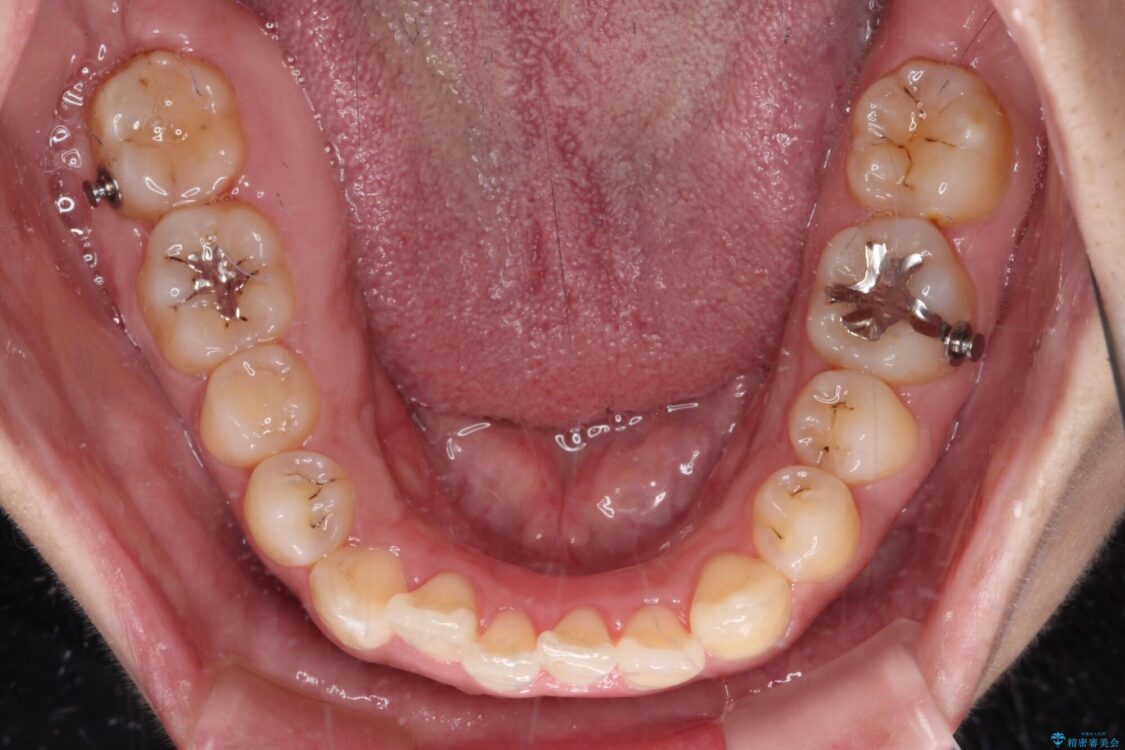

治療前

• 【モニター】カリエール・ディスタライザーを併用した八重歯のインビザライン矯正 治療前画像